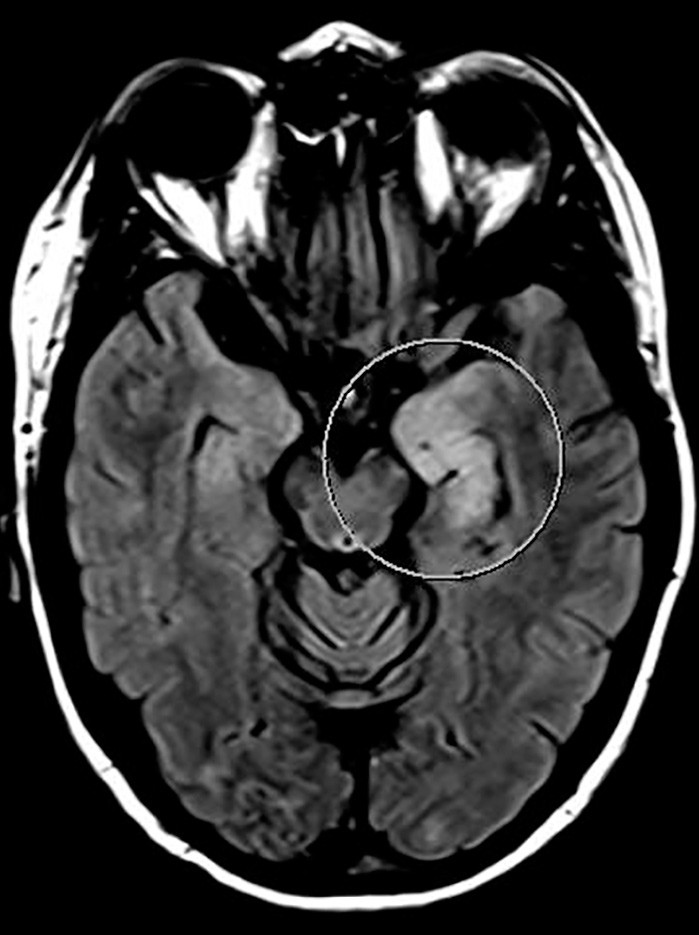

MR caput viste forandringer i mesencephalon, øvre del av pons og venstre cerebellarpedunkel, og i høyre hippocampus. Hjerneforandringene ble tolket som iskemiske lesjoner (fig 1). MR-angiografi var uten patologiske funn. Derimot var EEG patologisk, med intermitterende langsom thetaaktivitet frontotemporalt bilateralt. Enfotonstomografi (SPECT) viste nedsatt perfusjon i høyre cerebellarhemisfære og basalt temporalt på høyre side.

På bakgrunn av feber, forhøyet celletall i spinalvæsken og nevrologiske utfall hadde vi mistanke om uspesifikk viral eller bakteriell meningoencefalitt. Pasienten ble derfor behandlet både med antibiotika og antivirale midler, men behandlingen ble stoppet etter at mikrobiologiske prøver var negative. Dette inkluderte Borrelia-serologi både i serum og spinalvæske, noe som er ikke uvanlig etter vellykket behandling (2). Ved bakteriell meningoencefalitt er celletallet i spinalvæsken vanligvis sterkt forhøyet (gjerne over 1 000 hvite blodceller/mm³), glukoseratioen lav, og allmenntilstanden forverres raskt med feber og bevissthetsendring. Pasienten hadde imidlertid kun lett forhøyet celletall og normal glukoseratio. Bred utredning med tanke på autoimmun, inflammatorisk, infeksiøs og malign sykdom var uten positive resultater. Differensialdiagnostisk ble det vurdert om MR-funnet av iskemiske lesjoner kunne peke i retning av progressiv multifokal leukoencefalopati (PML), en demyeliniserende tilstand som oftest rammer immunsupprimerte pasienter grunnet reaktivering av JC-virus (3). Spinalvæskeundersøkelse hos vår pasient viste ikke funn av JC-virus, og derfor vurdert vi progressiv multifokal leukoencefalopati som lite sannsynlig. Tilstanden ble isteden oppfattet som et uveomeningealt syndrom. Dette er en inflammatorisk multisystemsykdom som affiserer øye, indre øre, hud og meninger (4).

I løpet av et par dager ble pasienten somnolent og fikk økende muskeltonus i alle fire ekstremiteter, økte reflekser og bilateral plantarinversjon. CRP steg til 130 mg/l (< 5 mg/l), leukocytter til 18 · 10⁶/l (4,5 · 10⁶/l) og SR til over 100 mm/h. Gjentatte spinalpunksjoner viste lett leukocytose (16 · 10⁶/l celler) og lett forhøyet totalprotein (0,66 mg/l). Isoelektrisk fokusering av spinalvæske var uten tegn til intratekal IgG-produksjon. EEG endret seg på seks dager fra nærmest normalt til svært patologisk, med generalisert høyspent, langsom theta- og deltaaktivitet samt hyppige, skarpe potensialer frontotemporalt med trifasisk utseende. MR caput viste progresjon av signalavvikene i mediale venstre temporallapp (amygdala, uncus og fremre hippocampus) i basalgangliene og subkortikalt i begge hemisfærer (fig 2a og b).

Signalforandringene i disse områdene var uten tegn til diffusjonsrestriksjon, noe som talte mot ferskt iskemisk infarkt. MR-bildene ga derimot mistanke om viral encefalitt eller limbisk encefalitt. Det var imidlertid ikke påvist affeksjon av insula, basale frontallapp og gyrus cinguli, som ofte er involvert ved limbiske encefalitter (6).